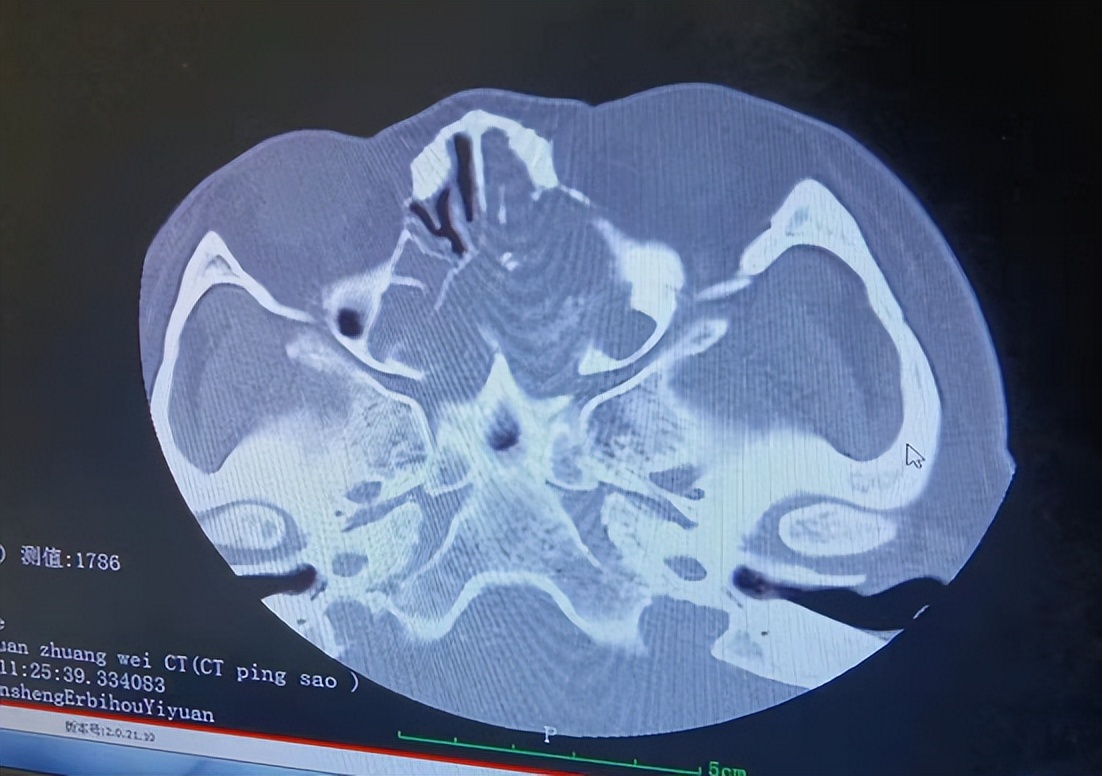

接诊后,我第一时间给患者做了详细地检查,发现患者左侧中鼻道有一半透明荔枝样新生物堵塞鼻孔,同时双侧下鼻道大量脓性分泌物,CT显示:鼻窦内部可见到颗粒状或斑点状高密度影,内有钙化灶,鼻窦内侧壁受压向中线移位,鼻中隔骨质连续性中断、变形,提示鼻腔及鼻窦占位性病变。

鼻窦内部可见不规则软组织密度影, 其中有斑点状钙化影,伴窦壁骨质增生及骨质破坏。